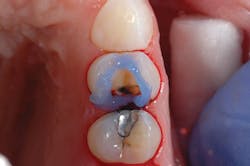

Figure 2: Selective enamel etching of tooth No. 12

After preparing the tooth, a viscous phosphoric acid gel was carefully traced around the margins of the preparation for a selective enamel etching technique and allowed to react for 15 seconds (figure 2). This was followed by copious water rinsing. Isolation was achieved using the Palodent Plus Sectional Matrix System (Dentsply Sirona), and Prime&Bond Elect was scrubbed over the entire preparation of tooth No. 12 followed by a gentle stream of oil-free air for five seconds to thin the material and evaporate the acetone solvent (figure 3).